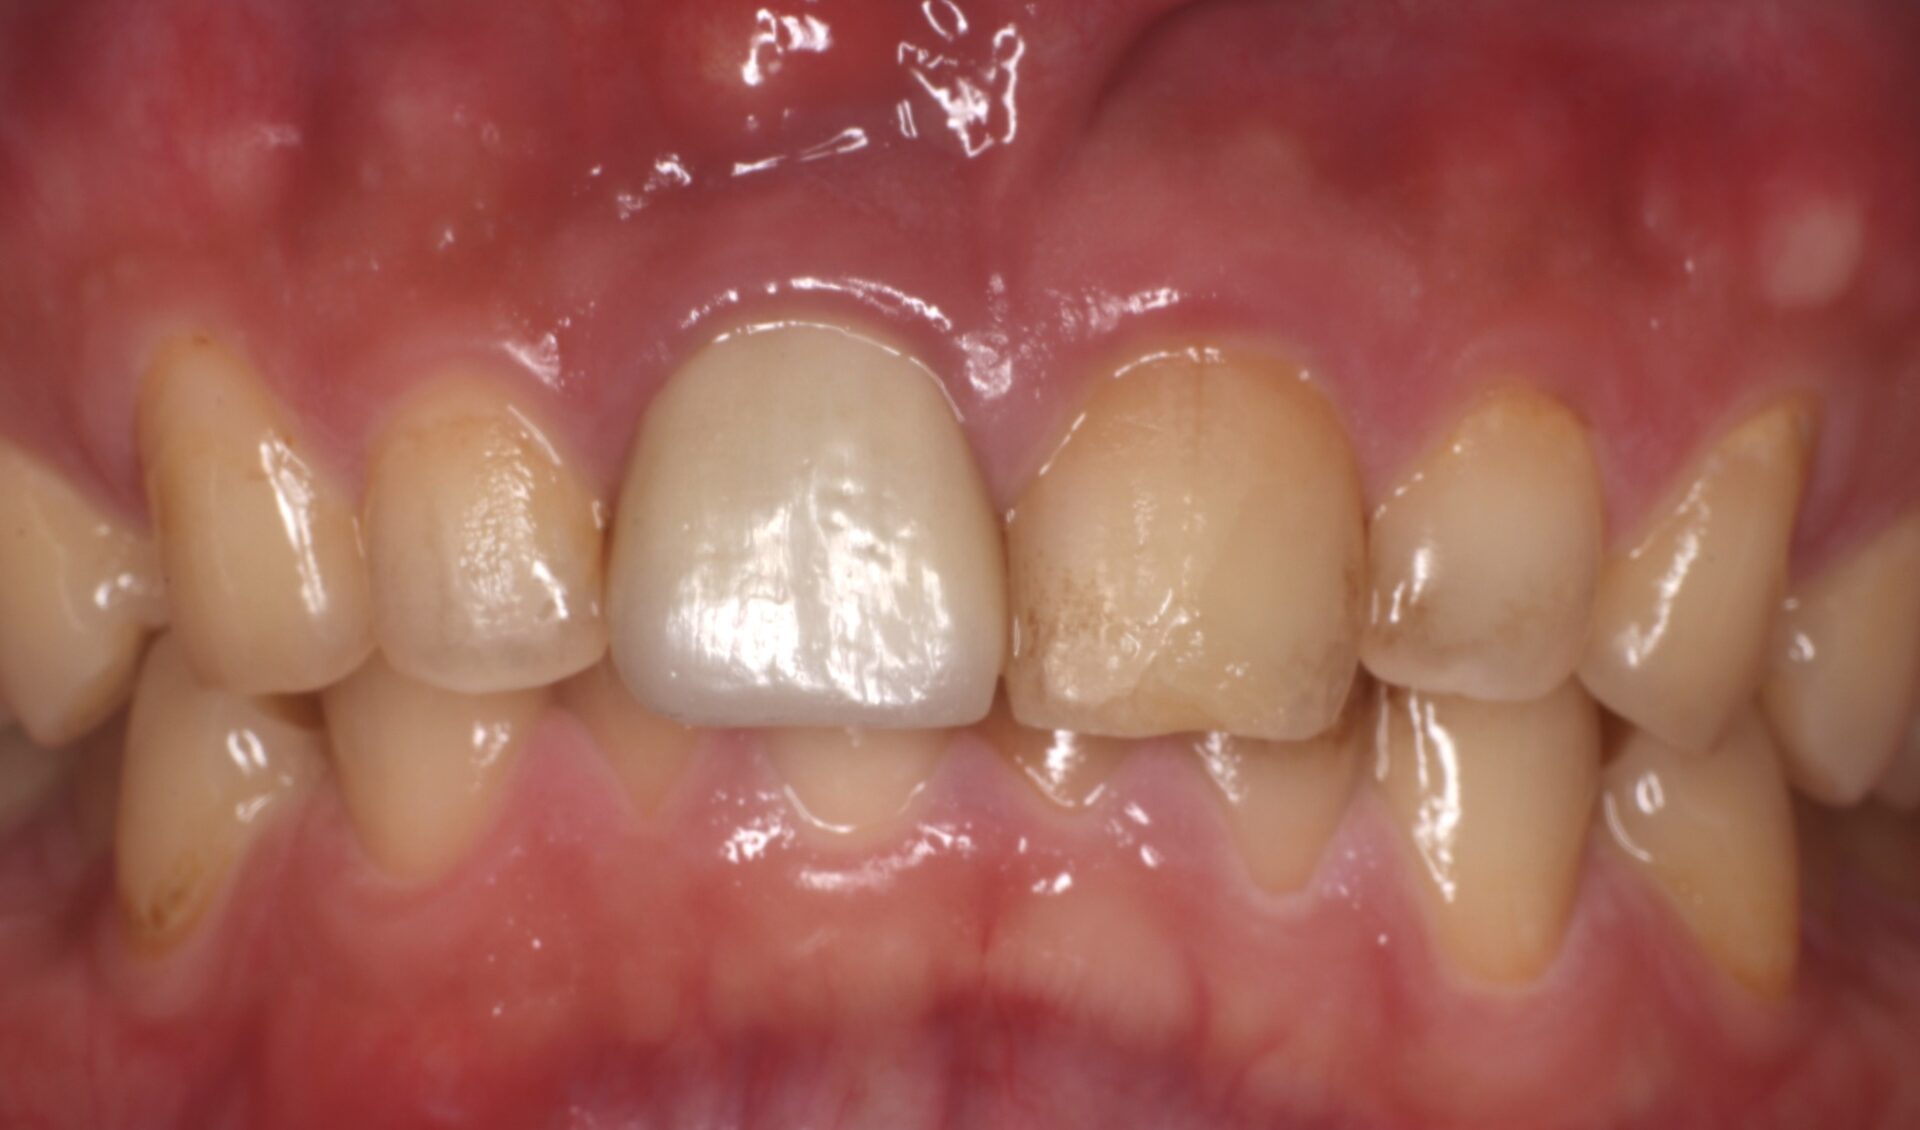

こちらは患者様のご希望でCTGを施行しなかった症例です。機能上は全く問題なく4年経過していますが天然歯である右側に比べるとインプラントである左側は歯肉が痩せているのが分かります。